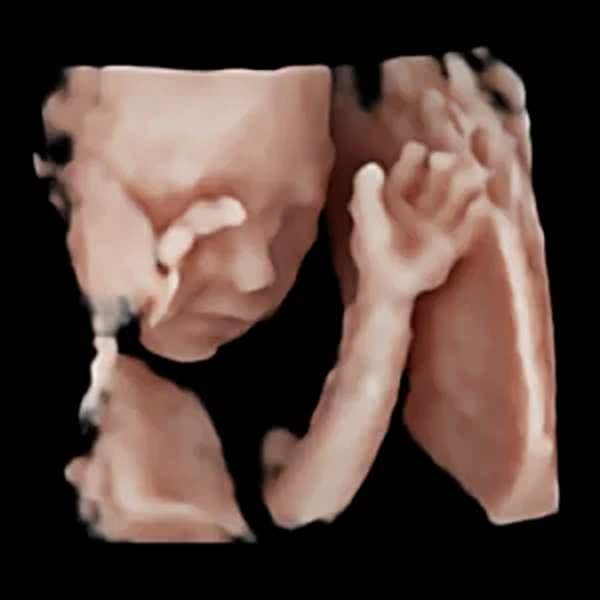

Ecografía 3D | 4D | 5D HDlive

La ecografía HDLive es una tecnología avanzada de ultrasonido en 3D y 4D que ofrece imágenes de alta resolución y realismo del feto durante el embarazo. Gracias a un sofisticado sistema de iluminación y sombreado, permite visualizar con gran detalle los rasgos faciales, movimientos y gestos del bebé en tiempo real. Es especialmente utilizada para mejorar la experiencia de los padres y facilitar la evaluación médica del desarrollo fetal. Segura e indolora, esta ecografía proporciona una visión más clara y emocionalmente impactante del bebé antes de su nacimiento.